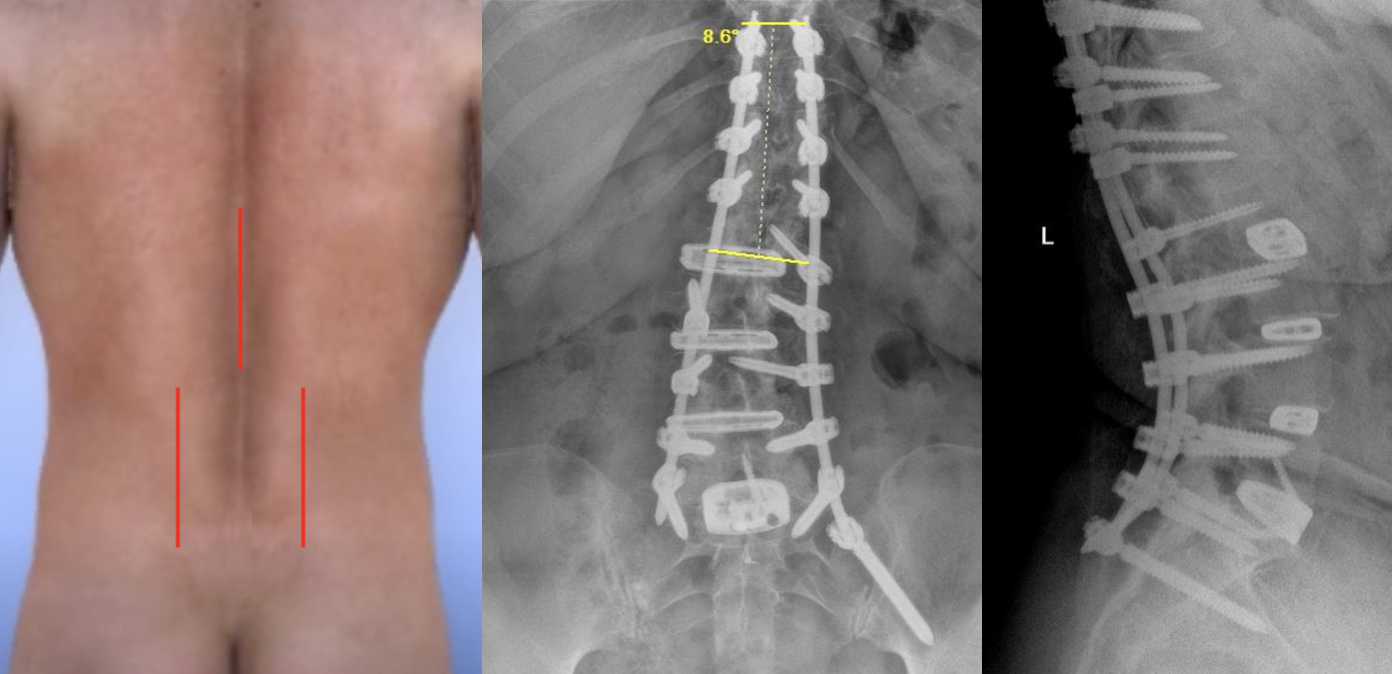

After:

Scoliosis Correction:

- Placing the cages creates a parallel space between the bones, correcting the scoliosis.

- Further correction of the scoliosis is achieved with the screws and rods.

- In some cases the fusion will be taken up to the T10 level with the screws and rods.